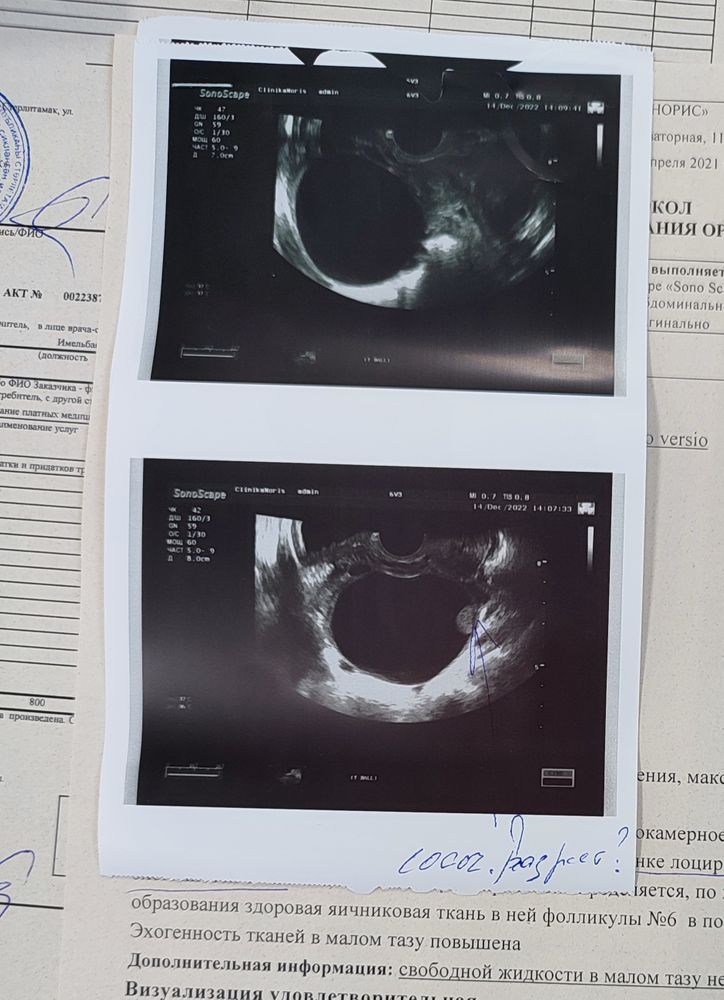

Неопределенная киста яичника

Девочки, помогите, может кто нибудь понимает в этой теме. Болит слева, тянетпоясницу и отдает сильно в ногу, пошла на узи, 10 д. Ц и на тебе, киста 7 см, что за киста определить не мргут, из за этого шарика внутри кисты, на что это похоже вообще? К врачу и на повторное узи к другосу чпециалисту пойду только 22 числа, но последние два дня все хуже и хуже чебя чувствую, переживаю